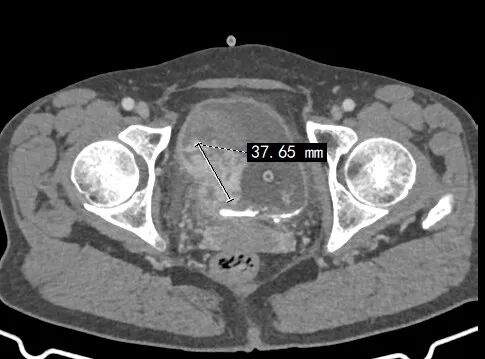

今年69岁的叶大爷(化姓)近半年频繁尿血,因为不痛他就没当回事。最近到十堰市人民医院泌尿外科就诊,被诊断为膀胱癌,大小约5公分肿瘤已经长到了膀胱肌层深部。

▲叶大爷膀胱癌术前片子